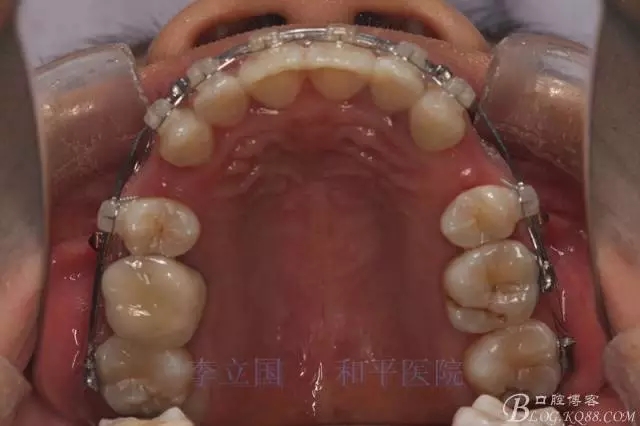

1.拔除14、24、31。

2.Damonclear排齊整平。

3.微種植支抗內(nèi)收上下前牙。

3.上頜應(yīng)用支抗釘。表麻下在56牙槽間隔植入,注意因使用的為鈦合金釘,一直保持植入角度與骨面成60度角,不要垂直植入再改變角度。要求即刻加載,即刻加載力值2盎司。